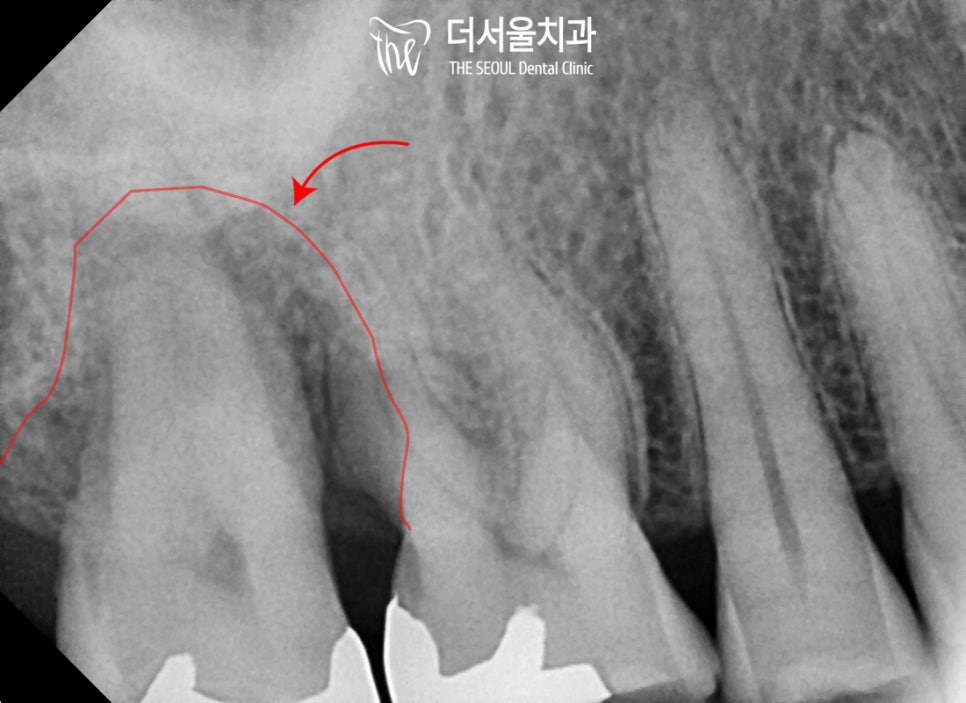

엑스레이를 살펴보면

상악 우측 제2대구치(#17)에

심한 골소실 소견을 보이고 있는데요,

이렇게 치조골이 많이 녹아버린 경우

주변을 잡아주는 치주 인대도 모두 소실되어

동요도가 발생합니다.